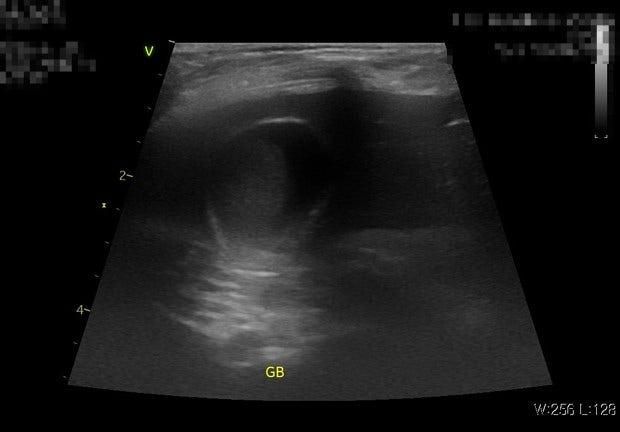

• 2번 째 사진